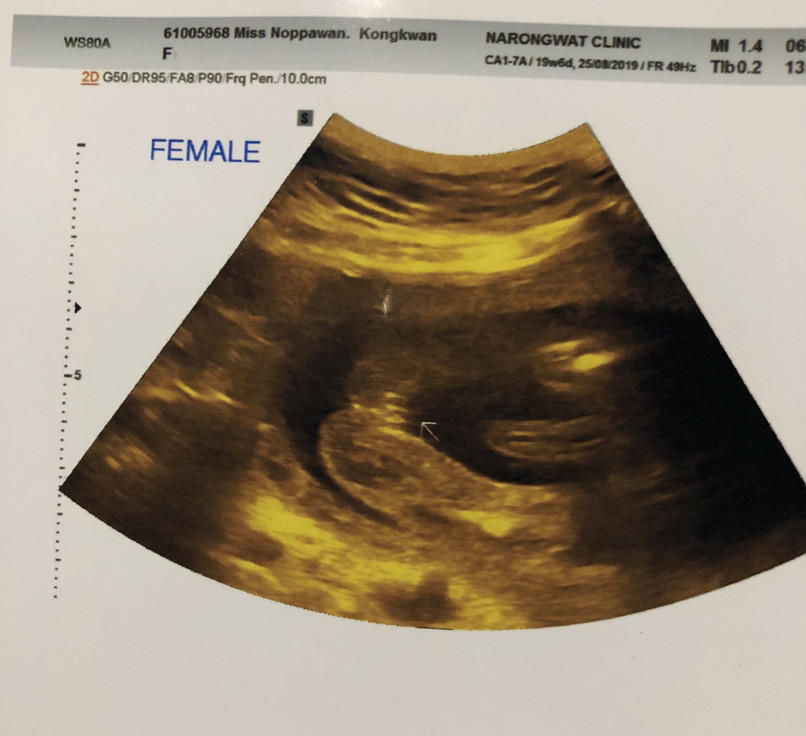

ญ จร้า

ผู้หญิง